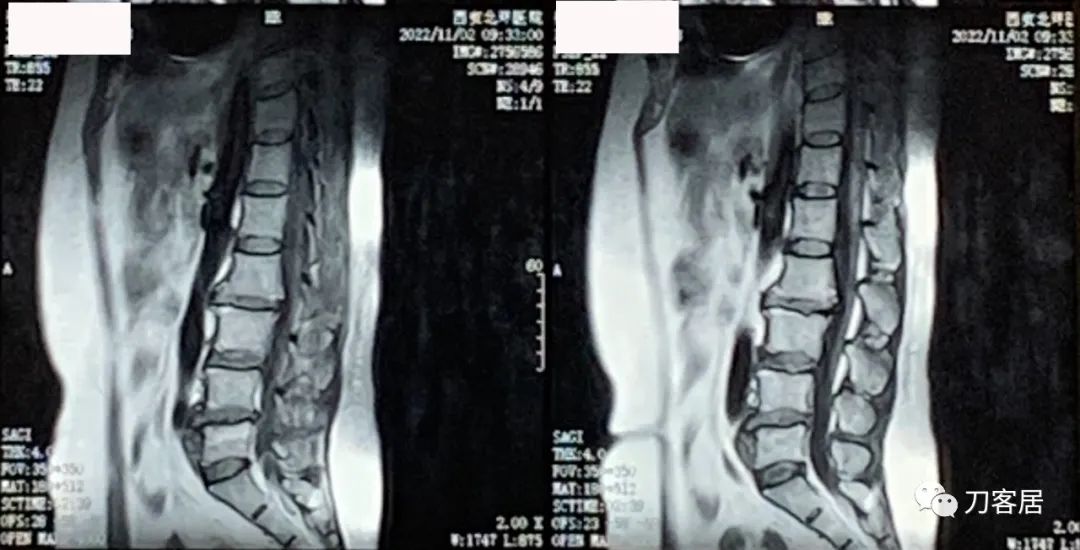

图2. 20221102西安北环医院腰椎MRI02

图3. 20221102西安北环医院腰椎MRI03